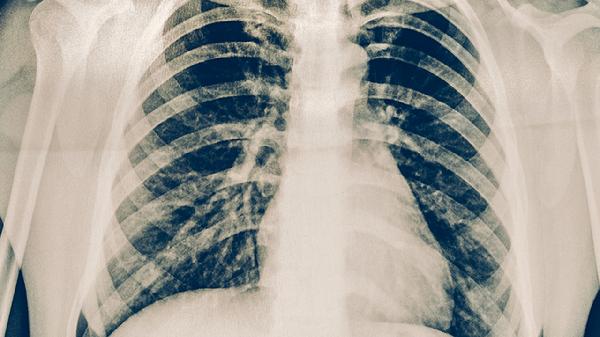

多根肋骨骨折伴明顯移位或連枷胸屬于危急情況。骨折斷端可能刺破胸膜導(dǎo)致氣胸,損傷肋間血管引發(fā)血胸,或刺傷肺組織造成血?dú)庑?。這類損傷常伴隨呼吸困難、皮下氣腫和反常呼吸運(yùn)動(dòng),需立即進(jìn)行胸腔閉式引流術(shù),必要時(shí)行肋骨內(nèi)固定術(shù)。嚴(yán)重并發(fā)癥可能引發(fā)呼吸衰竭或感染性休克,需在重癥監(jiān)護(hù)室進(jìn)行機(jī)械通氣和抗感染治療。

胸肋骨骨折后應(yīng)保持半臥位休息,避免平躺加重疼痛。飲食需增加高蛋白食物如魚肉、雞蛋促進(jìn)骨痂形成,同時(shí)補(bǔ)充維生素D鈣片。恢復(fù)期間定期復(fù)查胸部X線片觀察愈合情況,若出現(xiàn)發(fā)熱、咳血或呼吸困難加重須立即就醫(yī)。吸煙患者必須戒煙,防止咳嗽影響骨折愈合。